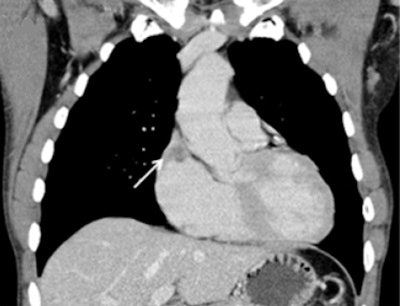

Metastases along the endocardium with polypoid growth into cardiac cavities were classified as endocardial metastases, and these patients were assigned to group 1. Metastases located in the myocardium with infiltrative growth were classified as myocardial metastases, and patients were assigned to group 2. Patients with metastases of the pericardium were assigned to group 3.

Fourteen out of 25 patients presented with singular cardiac mass (56%), whereas 10 patients (40%) presented with multifocal metastases, and one patient with disseminated metastases. Twelve patients presented with endocardial (48%), eight with myocardial, and two with pericardial metastases. The most frequent site involved in endocardial metastases was the right atrium (67%), followed by the right ventricle (33%).